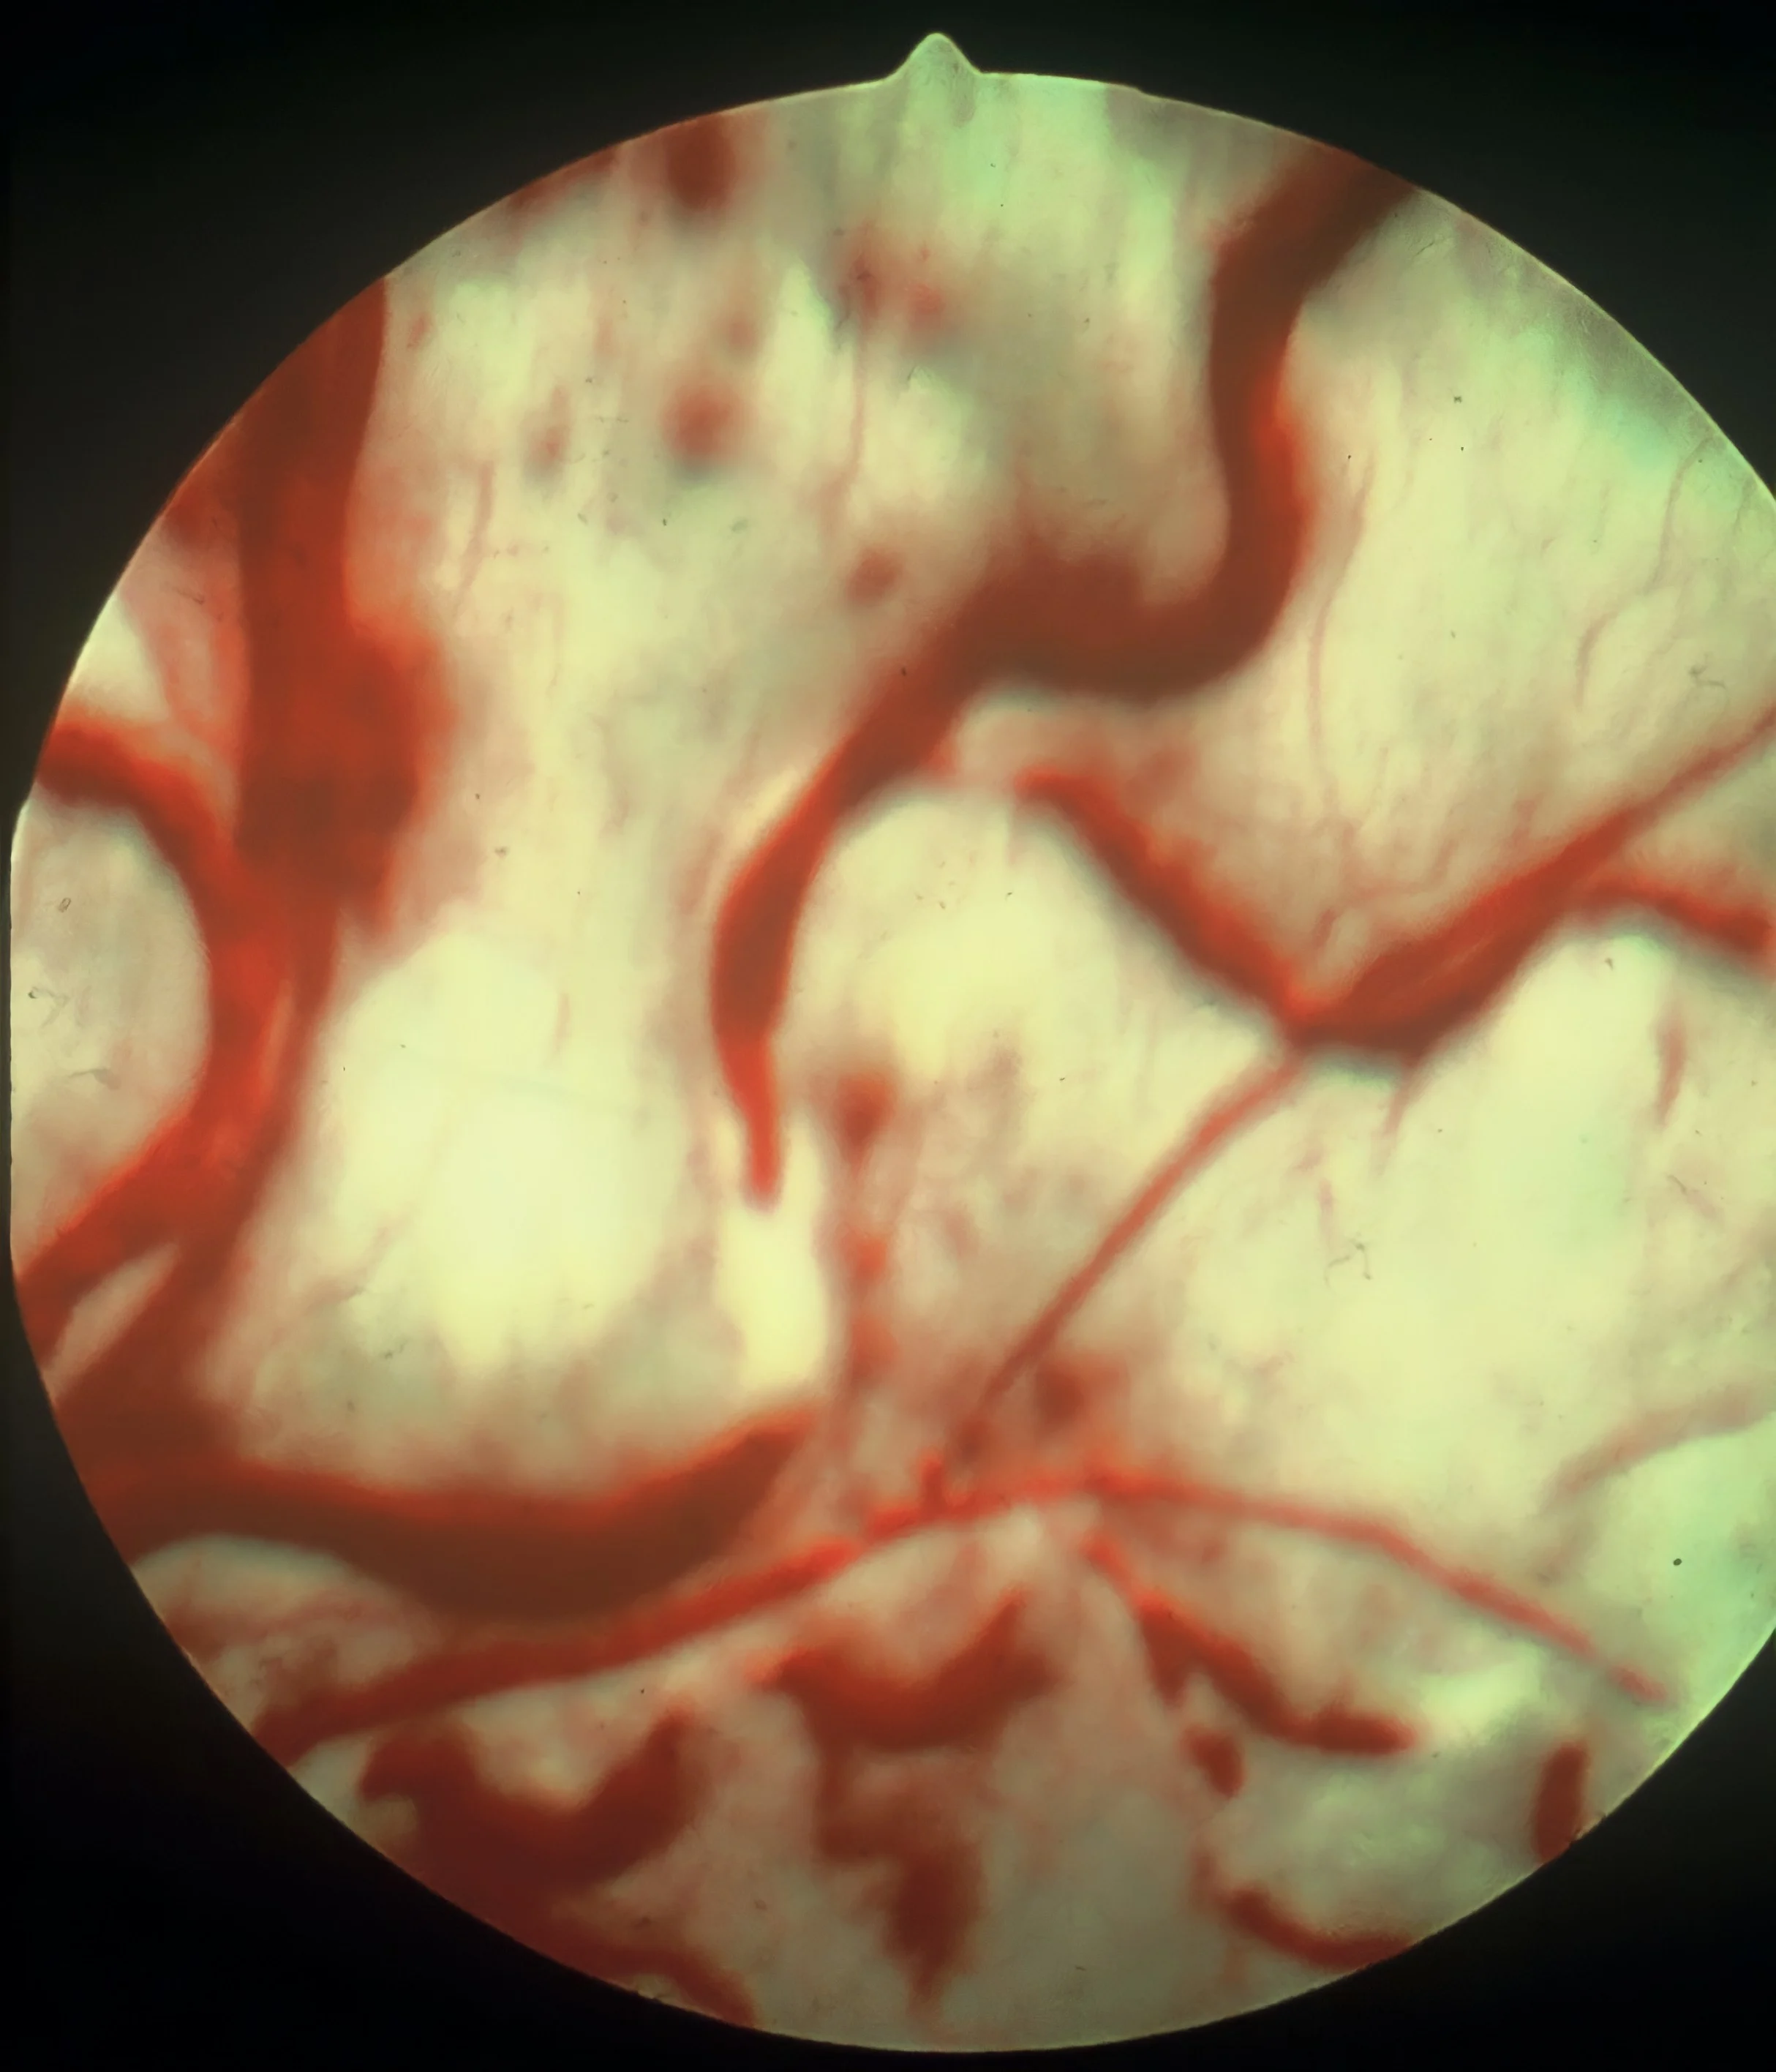

2. Retinal Hemorrhage

Retinal hemorrhage is a common sequela to hypertension.1 Hemorrhages may be focal, multifocal, or large hemorrhagic subretinal areas (Figures 3 and 4). The mechanism is related to arteriolar vascular permeability changes.8,9 Autoregulatory mechanisms cause initial vasoconstriction, followed by possible arteriole lumen occlusion and ischemic necrosis. Increased vascular permeability can affect the choroid and cause subretinal fluid and retinal detachment.8,9

Retinal hemorrhages are also common with other conditions (eg, trauma, infectious disease, coagulopathy, neoplasia, diabetes, congenital disorders) that cause vasculitis, as well as hyperviscosity syndrome.8 In dogs, tick-borne diseases are infectious agents that can be associated with retinal hemorrhage.8

Differential diagnoses for retinal hemorrhage are coagulopathy, infectious disease, neoplasia, trauma, congenital disorders, and hyperviscosity syndrome secondary to multiple myeloma.